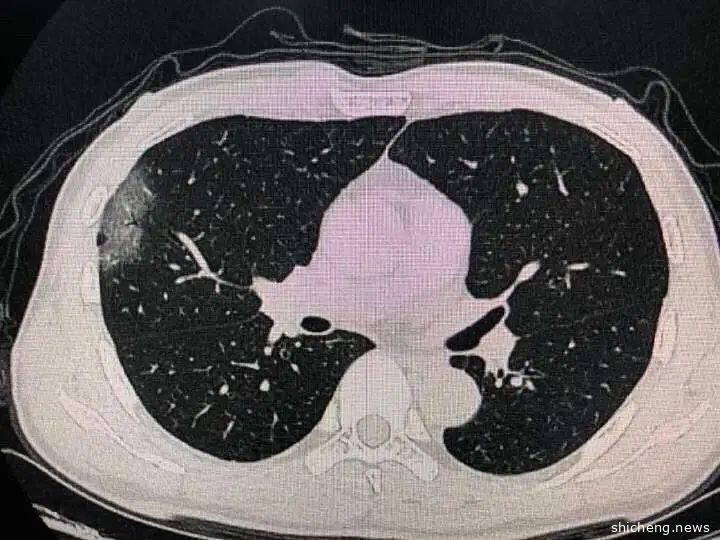

较轻一些的症状则是肺功能轻微受损,出现呼吸急促,咳嗽等症状,还有患者出现胃痛、易疲劳、肌肉酸痛等症状。体力一日不如一日。

只要病人没有基础性疾病,恢复就会很快,出院后恢复的也会不错,即使有基础性疾病,也会比非典好一些,17年前的非典,有些病人半年到一年后还有肺部纤维化,新冠肺炎患者肺部纤维化不会太严重,虽然对一些病人做了肺功能检查后,还没有回复道行唱的水平,但是看起来损害不会太重,慢慢都会恢复,后遗症不大。